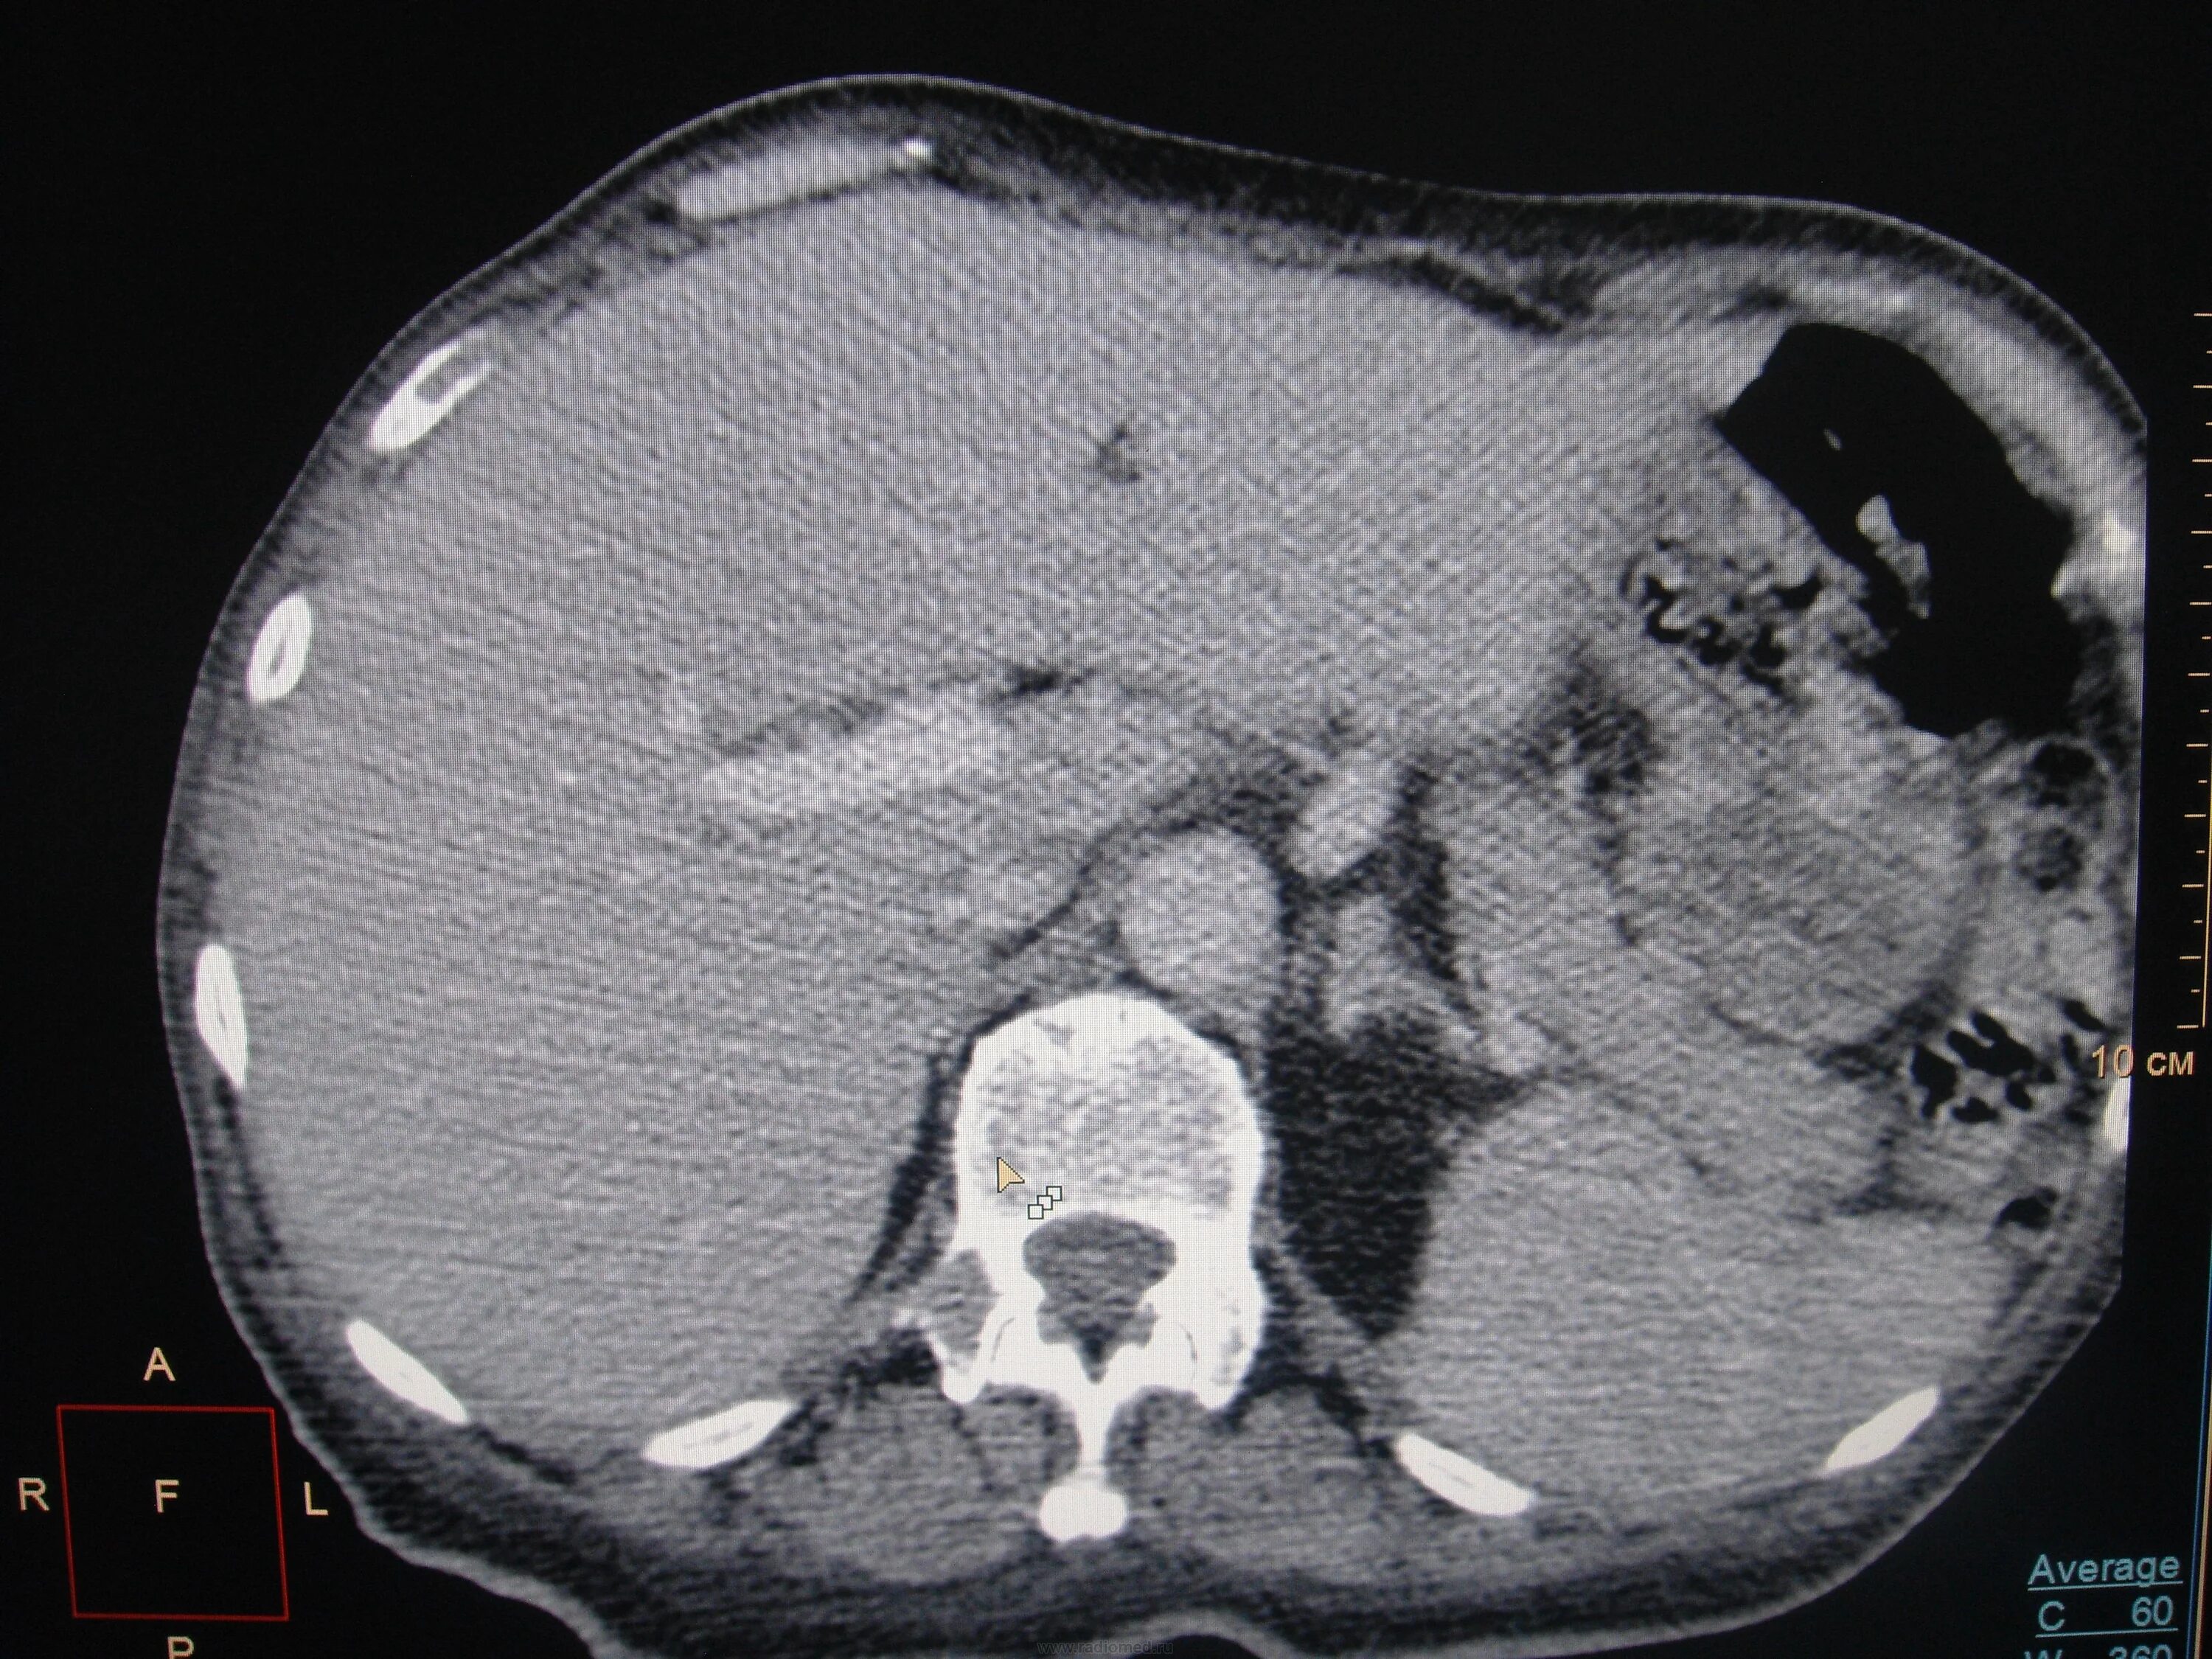

Метастазы костей мрт